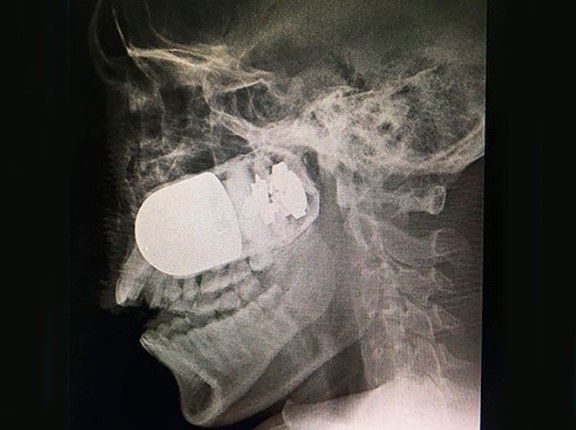

El pasado 5 de junio se realizó una peligrosa intervención quirúrgica en al exterior de las instalaciones del Hospital Militar de Bogotá, en Colombia, luego de que horas antes, por la mañana, un compañero de un soldado manipuló sin cuidado un lanzagranadas MGL y lo activó accidentalmente provocando que una granada de asalto M-40 se le incrustara en lóbulo derecho al militar Leandro José Luna.

En un primer momento, el soldado fue llevado al hospital de Tame, pero como este no contaba con los elementos suficientes para extraer la granada, fue trasladado por carretera a Bogotá, en un trayecto que duró ocho horas, pues llevarlo en un helicóptero implicabaa el riesgo de un accidente peor.

“En cuanto llegó, se activaron los protocolos de seguridad; entre ellos, alejar a las personas 10 metros a la redonda. Era vital realizarle una traqueotomía para que respirara correctamente. Todo se hizo simultáneamente, con mucho cuidado y profesionalismo. Los cortes y la presión para retirar el artefacto debían ser muy exactos. En cuanto retiramos la granada, hicimos limpieza en el área y lo subimos a las salas de cirugía”, informó el cirujano Maldonado.